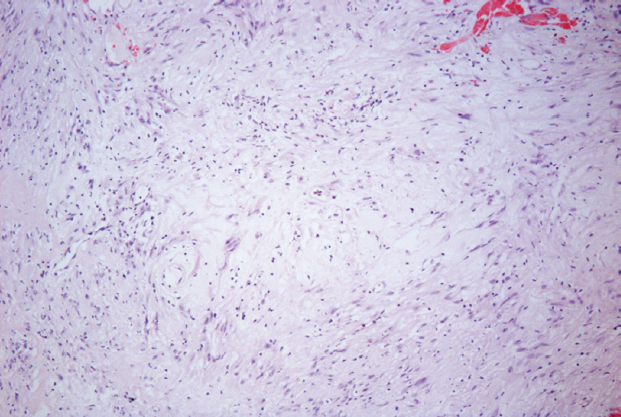

Рис. 8. Гистологическая картина нейрофибромы. На фотографии представлена опухоль периферического нерва из клеток с небольшими овальными ядрами и хорошо различимыми клеточными отростками, продемонстрированы структуры по типу «тертой моркови». Окрашивание гематоксилином и эозином, ×100

Fig. 8. Histological picture of neurofibroma. The photograph shows a tumor of the peripheral nerve from cells with small oval nuclei and well-defined cellular processes, structures like “grated carrots” are demonstrated. Staining with hematoxylin and eosin, ×100

По данным гистологического исследования операционного материала опухоль представлена преимущественно веретеновидными клетками, формирующими разнонаправленные пучковые структуры. Выявляются участки, в которых ядра и сонаправленные им соединительнотканные волокна (позитивное окрашивание по методу Ван-Гизона) приобретают волнистое строение с небольшими фокусами по типу «тертой моркови». Отмечается тенденция к формированию псевдо-мейснеровских телец. По краю опухоли более выраженное формирование грубоволокнистой ткани. Митозы не обнаружены (рис. 9). Заключение — нейрофиброма (Grade I).